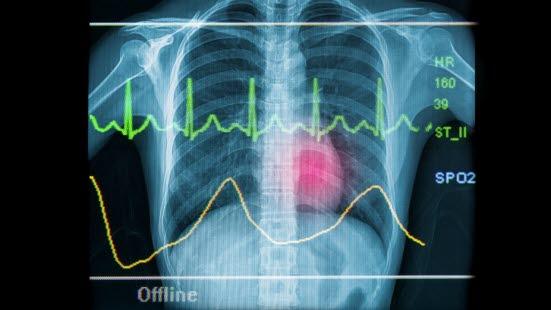

EKG ved angina og hjerteinfarkt

Ved angina er hvile-EKG normalt. Ved hjerteinfarkt derimot viser EKG unormale forandringer i hvile.

Når et område av hjertemuskelen har for dårlig blodtilførsel, gir det forandringer på EKG. Det synes i den delen av EKG'et som betegnes ST-segmentet. Oksygenmangel i et område av hjertemuskelen vil vises som et senket ST-segment. Ved å granske hvilke avledninger ST-senkningen forekommer i, kan man si hvor omtrent problemet sitter og kanskje også hvilken koronararterie som er trang.

Ved hjerteinfarkt vil et område av hjertemuskelen dø og etter hvert erstattes med bindevev som er uten evne til å bidra med kraft til sammentrekningen av hjertet (se illustrasjon av hjerteinfarkt). Denne skaden av hjertet gir flere forandringer på EKG. Den første forandringen som observeres, er at ST-segmentet blir hevet. Dernest kan det dannes en ny Q-bølge. Senere kan man observere at T-bølgen snur (blir invertert) - i stedet for å gå oppover går den nedover. Mens ST-forandringene er forbigående, er forandringene i Q- og T-bølgene som regel varige, og de kan brukes til å påvise "gamle" infarkt. Akkurat som ved angina pectoris kan legene ved å konstatere i hvilke avledninger forandringene forekommer, fastslå hvor i hjertet infarktet er.